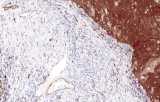

A patologia ginecológica é a subespecialidade médica focada no diagnóstico de doenças do trato genital feminino, abrangendo desde adenocarcinomas endocervicais até tumores de células germinativas ovarianas. Os cinco cancros ginecológicos primários são o cancro do ovário, endométrio/útero, colo do útero, vulva e vagina, cada um com etiologias e fatores de risco distintos, incluindo idade, história familiar e influências hormonais.

A imunohistoquímica (IHQ) com anticorpos primários CE/IVD é essencial para o diagnóstico e classificação precisos de malignidades ginecológicas e mamárias. Estes anticorpos permitem a deteção precisa de marcadores tumorais e proteínas celulares, apoiando o diagnóstico diferencial e guiando estratégias terapêuticas personalizadas.

Estudos recentes destacam o valor diagnóstico das proteínas do complexo SWI/SNF, particularmente ARID1B, na identificação de malignidades ginecológicas desdiferenciadas e indiferenciadas – tumores agressivos com mau prognóstico. A IHQ de ARID1B oferece elevada especificidade e está cada vez mais integrada em painéis diagnósticos para melhorar a precisão. Painéis com marcadores adicionais também apoiam a diferenciação de sarcomas uterinos, aumentando a exatidão diagnóstica. Evidência emergente sugere que ARID1B pode representar um alvo terapêutico potencial no carcinoma ovárico de células claras, embora as aplicações clínicas permaneçam em fase investigacional.